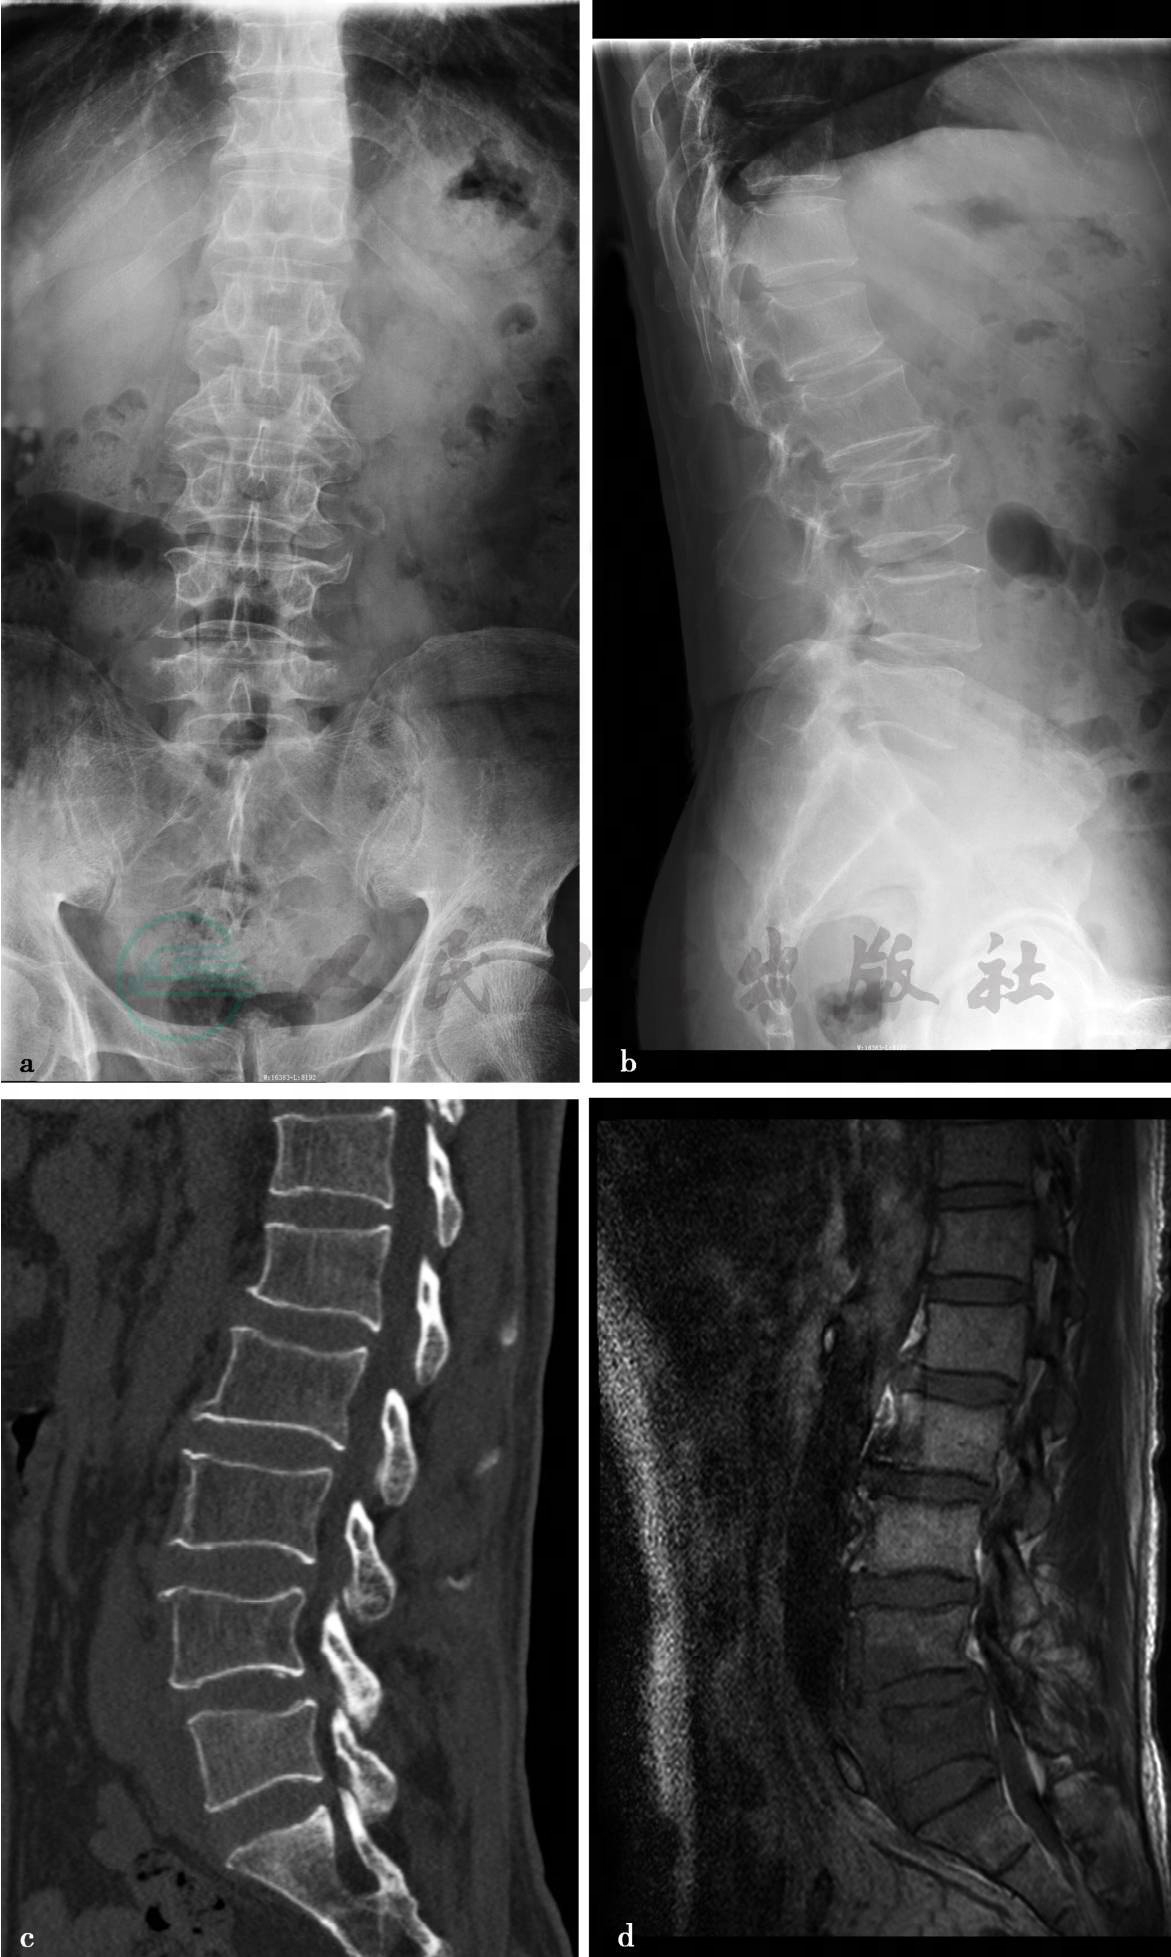

病例2:X线、CT平扫及MRI平扫、增强扫描。

图1 图1a、b,腰椎正侧位示腰椎退行性改变。图1c,腰椎CT矢状位重建(骨窗)示L5椎体骨质密度欠均匀,L4-5椎旁可见软组织密度影。图1d,腰椎MRI平扫示T1WI。图1e,T2WI示L4、L5椎体呈长T1长T2信号,L4/5椎间盘信号略减低,椎体周围可见长T1长T2信号环绕,与两侧腰大肌分解不清。图1f,腰椎MRI轴位增强图像示病变椎体及周围异常信号影明显强化